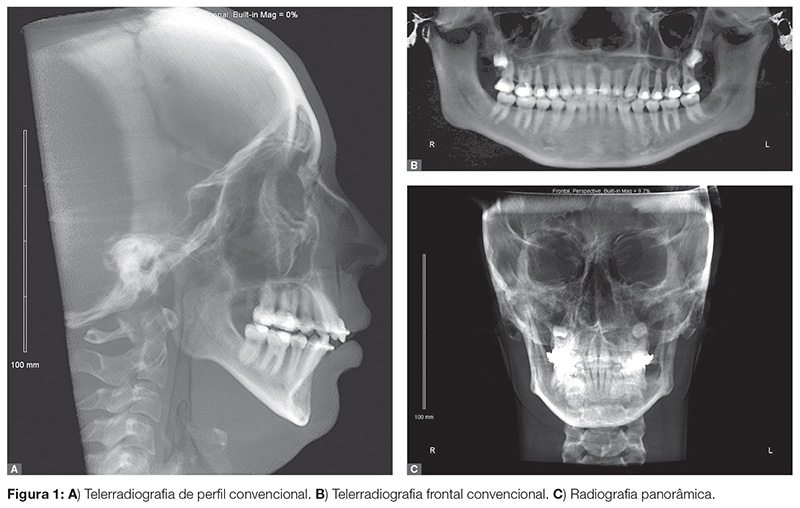

Múltiplas projeções radiográficas (perfil, frontal, panorâmica) ainda são usadas em uma tentativa de se visualizar relações anatômicas complexas (Fig. 1). Mas, na prática, a interpretação de múltiplas imagens é difícil para o clínico com menos formação e entendimento na área de Radiologia. Com a introdução do uso de tomografias, em especial a TCFC, a visualização dessas estruturas em 3D é, hoje, mais fácil e acessível. Porém, muita discussão ainda existe a respeito da indicação rotineira das TCFC para o diagnóstico e plano de tratamento ortodôntico. Exposição à radiação, vantagens das imagens obtidas em relação às convencionais, facilidade de acesso a equipamentos de tomografia, e o custo são considerações a serem feitas.